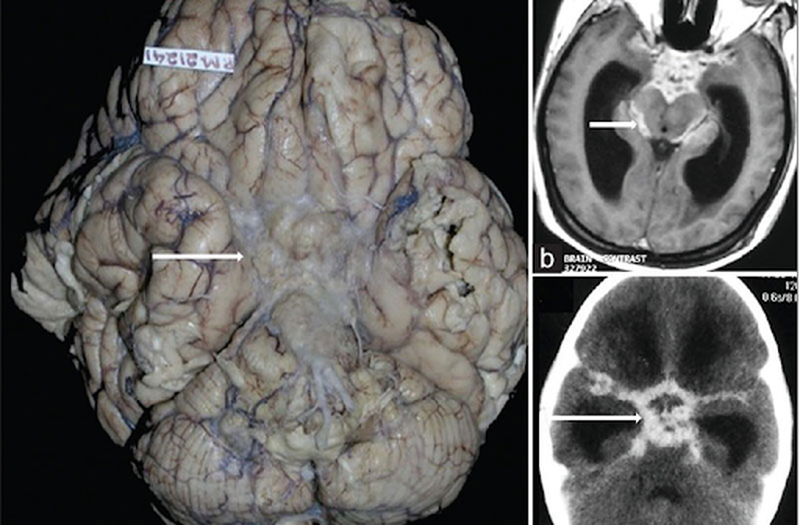

lao màng não điều trị bao lâu 1 Căn bệnh lao màng não ngày nay có chữa được hay không

Lao màng não là một căn bệnh nguy hiểm, nó gây nên tấn công theo đường máu và đi trực tiếp vào bộ não của con người. Căn bệnh này có thể gây tử vong nếu người bệnh không được điều trị kịp thời.